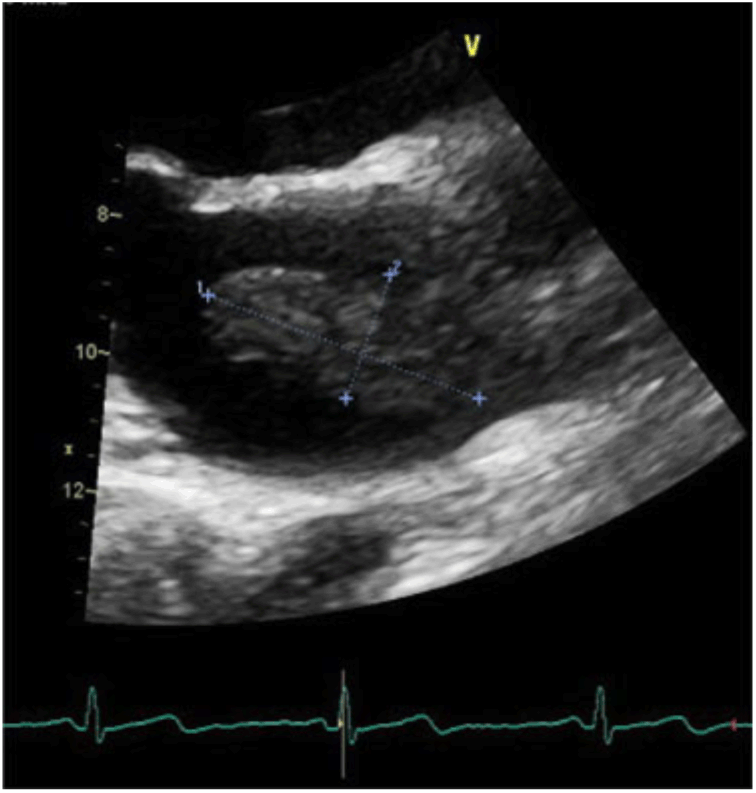

After 10 months, the patient presented again to hospital with a 1-week history of thunderclap headache followed by right-sided ptosis and inferolateral deviation of the right eye. Physical examination demonstrated a complete right cranial nerve III palsy. Cardiovascular examination demonstrated a 2/6 systolic ejection murmur at the left upper sternal border, new from previous, but otherwise normal findings. MRI of the brain demonstrated no change from previous or evidence of acute infarct. CTA of the head and neck demonstrated a right posterior communicating artery (Pcomm) aneurysm (Figure 1), which was very subtle in retrospective review of the CTA at initial presentation, 10 months prior. Neurosurgical consultation led to right Pcomm aneurysm clipping. TTE was subsequently performed to investigate potential causes of embolization and revealed a left atrial mass (Figure 2). CT of the chest was done to further characterize the mass, suggesting a diagnosis of atrial myxoma. After several weeks, the patient underwent open-heart surgery for mass resection. Pathology confirmed the diagnosis of atrial myxoma. Further history did not reveal personal or family history of aneurysms or disorders associated with cerebral aneurysm formation, such as Ehlers–Danlos syndrome or autosomal dominant polycystic kidney disease. The patient was discharged having experienced no recurrent embolic phenomena.

Figure 2: TTE discovered left atrial mass seized 1.9 cm x 4.9 cm.